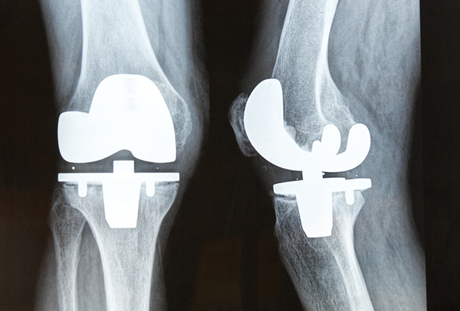

Mar tige enthousiast ferteld se wat ùs te wachtsjen stiet. Der wurd in film draait oer in nepoperaasje wer`t gjin drip bloed oan te pas komt. Mar dochs komt it my hiel realistysk oer. It sikenhûs is oan it ferbouwen en de wurklju binne bûten oan it seagjen en boarjen dat hearren en sjen jin fergiet. By it sjen fan de knibbelfilm en it lûd op de eftergrûn giet in man oerein: “It hoecht om my net mear..” seit er en giet foart.

Mar de rest bliuwt sitten. We sjoche mekoar es oan en freegje ùs ôf wat moatte wy dan mei de âlde knibbels?